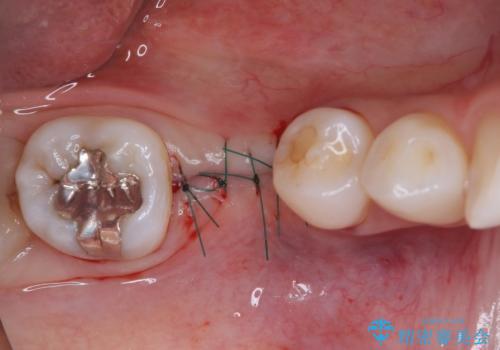

- 近医で奥歯の抜歯が必要であると指摘され、インプラント治療を希望して来院された患者様です。

診察の結果、歯が破折しており抜歯が必要でした。

抜歯後にはストローマンSLActiveを埋入し、補綴治療を行うこととしました。

機能性と清掃性、更には審美性も考慮し、土台となるアバットメントにはジルコニアカスタムアバットメントを採用しました。

ジルコニアカスタムアバットメントは、歯肉ラインに金属が見えにくいというだけでなく、クラウンを装着する土台の形が天然歯と近い形態となるため、清掃性が高く歯肉が腫れにくいというメリットがあります。